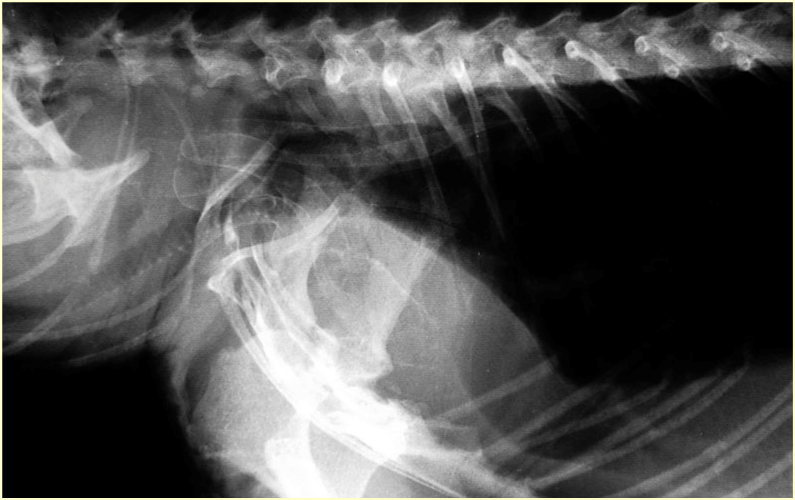

X線検査は、進行した動脈硬化症の最も明確な非侵襲的証拠である血管石灰化の存在を確認するために使用されます。特に、腹部大動脈や腎動脈領域に沿った石灰化の像は、代謝性骨疾患に起因する血管硬化の強力な証拠となります。